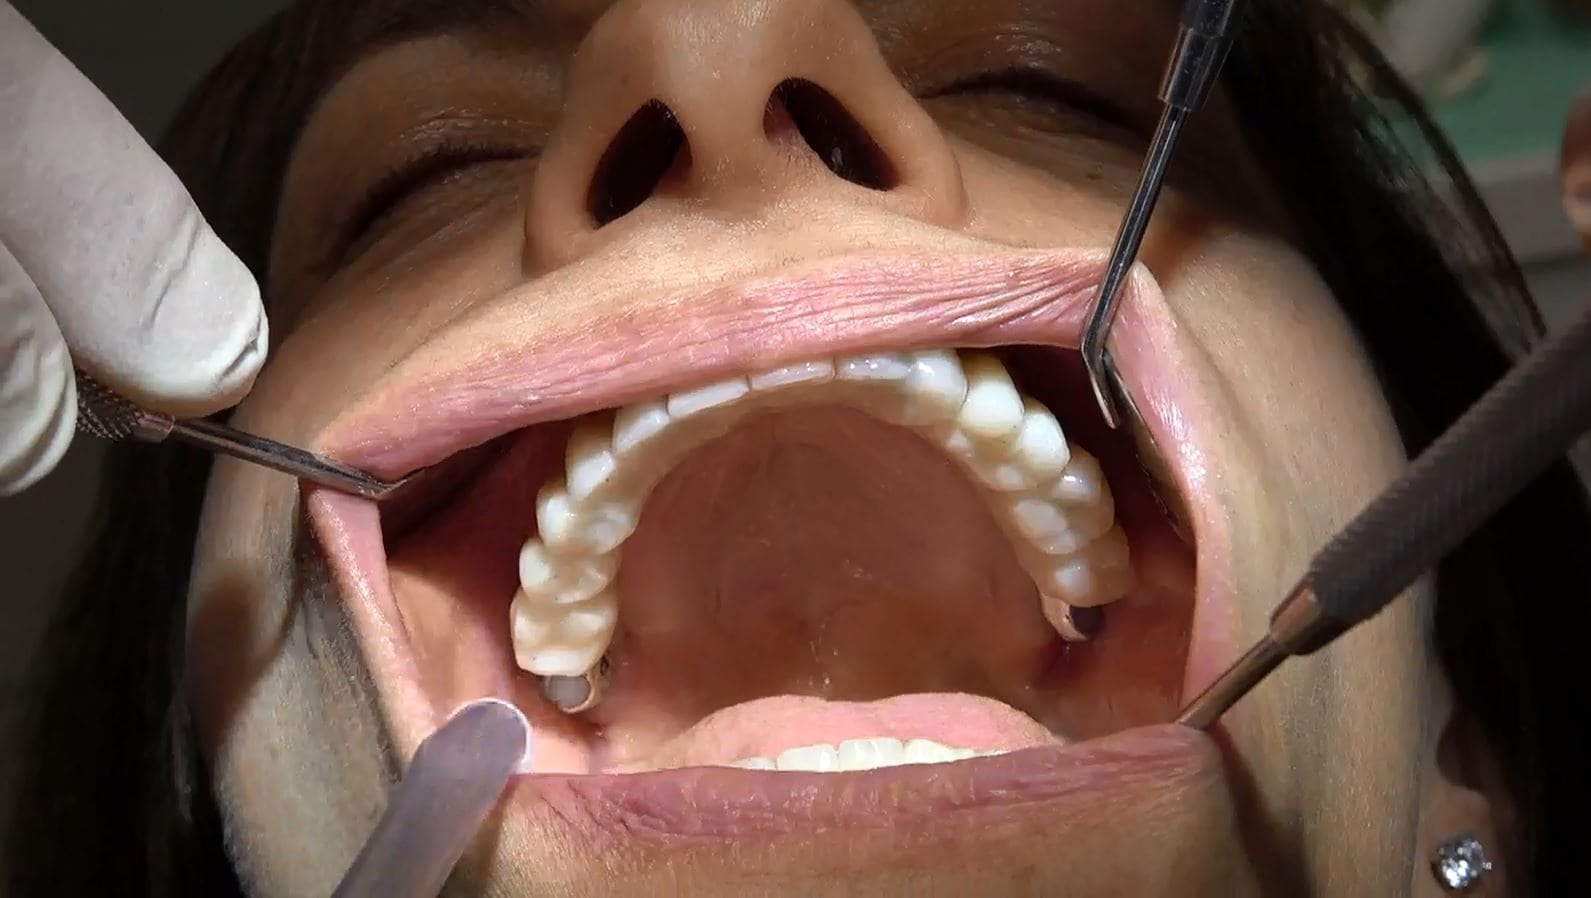

Siamo entusiasti di presentarvi un affascinante caso video proveniente dal nostro avanzato centro specialistico. Questo caso coinvolge una paziente proveniente dalla bellissima Sardegna, portatrice di una protesi removibile da ben 30 anni. La sua situazione era giunta a un punto critico, con un livello di riassorbimento osseo così estremo che rendeva difficile persino il supporto della dentiera.

La decisione di affidarsi alla nostra struttura altamente specializzata è stata fondamentale per trovare soluzioni fisse per pazienti con gravi atrofie ossee, coinvolgendo sia il mascellare che la mandibola. Dopo una lunga e approfondita valutazione delle condizioni ossee residue, abbiamo scelto di adottare la tecnica avanzata dell’implantologia sottoperiostea.

PAZIENTE PASSA DA 30 ANNI DI DENTIERA A DENTI FISSI PROVVISORI POI DEFINITIVI NEL GIRO DI UN ORA E TRENTA MINUTI